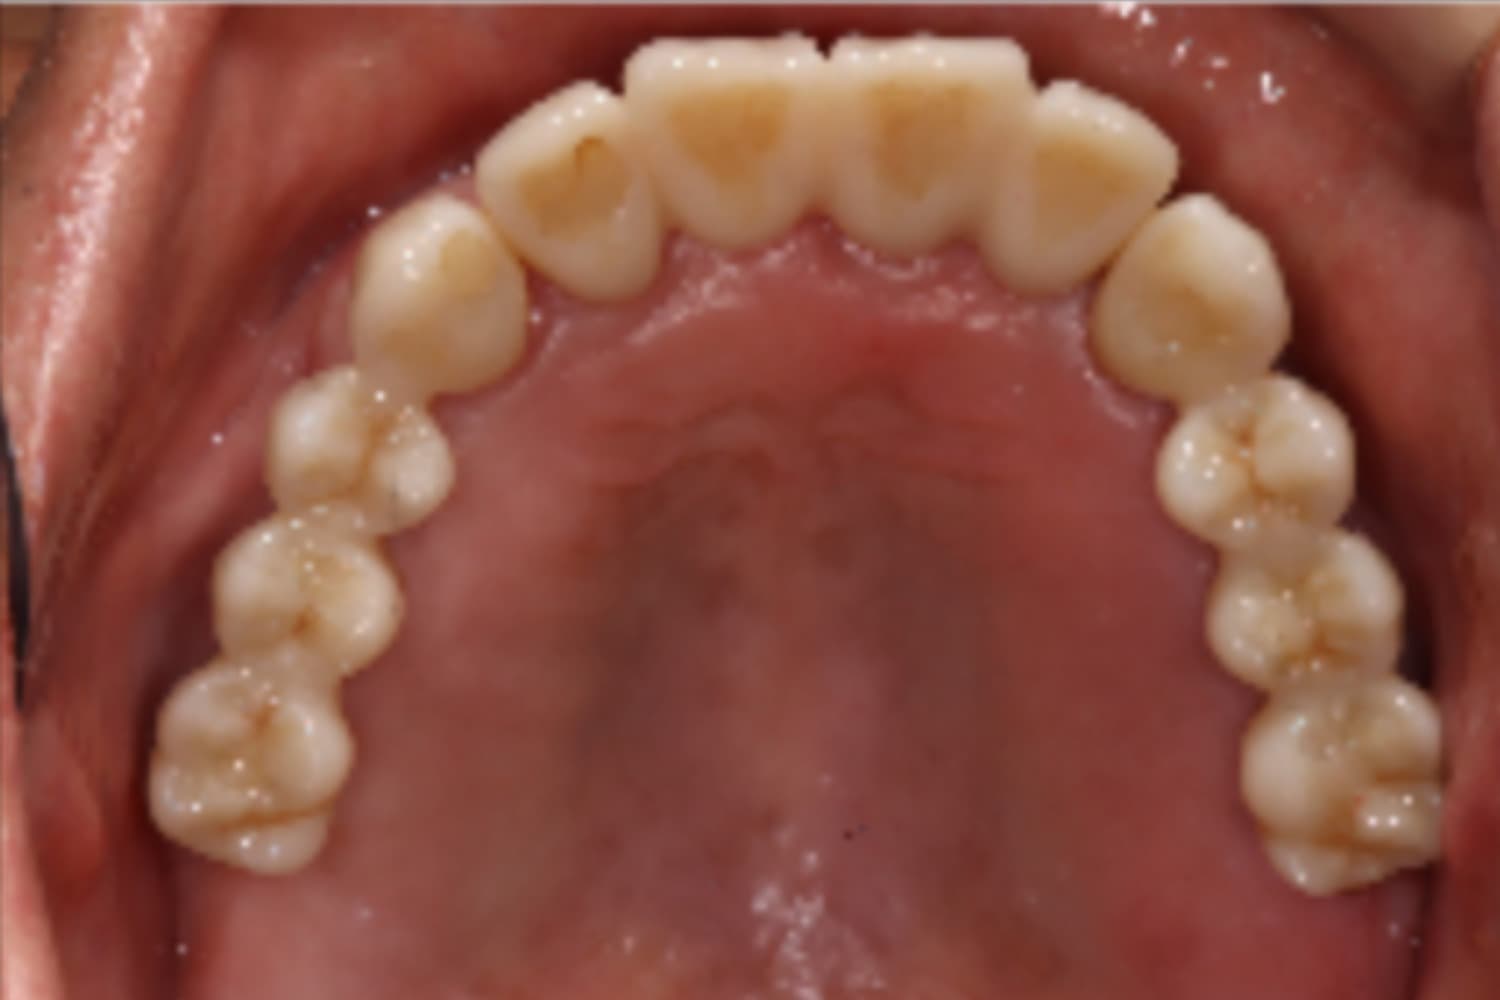

上顎欠損部のインプラント治療

Before

After

上顎欠損部にインプラントを行い、上顎前歯にはセラミックを装着

主訴

物が噛みづらい

治療期間

26カ月

治療回数

26回

費用

3,360,000円

副作用・リスク

・上顎洞炎を発症する可能性がある